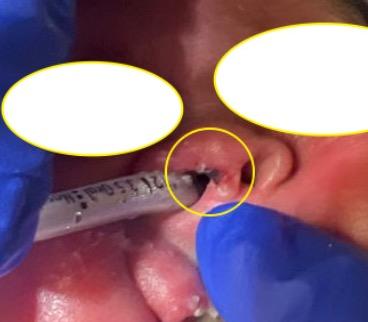

Pressure injury at the Columella caused by bubble continuous positive airway pressure device.

A: Stage 2 or 3 pressure injury; difficult to visualize but depth is 0.2 cm. Cartilage not visible. B: Same nasal injury after healing.

Most pressure injuries in the NICU are related to nasal prongs (e.g., Hudson Prongs).

Prevent injury by:

• Offloading the prongs and tubing set every 3 hours or with cares.

• Removing any moisture from the tubing, prongs, and babies’ faces.

• Using assistive devices such as velcro clips, “arms” for isolettes, or jellies to secure heavy CPAP tubing in place.

• Ensuring the proper size of nasal prongs are used.